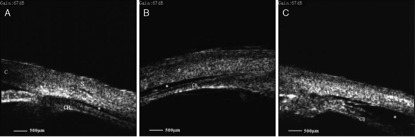

该研究主要通过 UBM 显示的脉络膜和巩膜之间间隙大小评估葡萄膜渗漏情况。渗漏根据 UBM 表现分为三级(图 1):0 级,无间隙;1 级,裂隙状(睫状体上间隙小于睫状体厚度的 1/2);2 级,带状(睫状体上间隙大于睫状体厚度的 1/2);3 级,显著(睫状体上间隙大于睫状体厚度)。

图 1 为 UBM 评估葡萄膜渗漏的分级,A:1 级葡萄膜渗漏;B:2 级葡萄膜渗漏;C:3 级葡萄膜渗漏